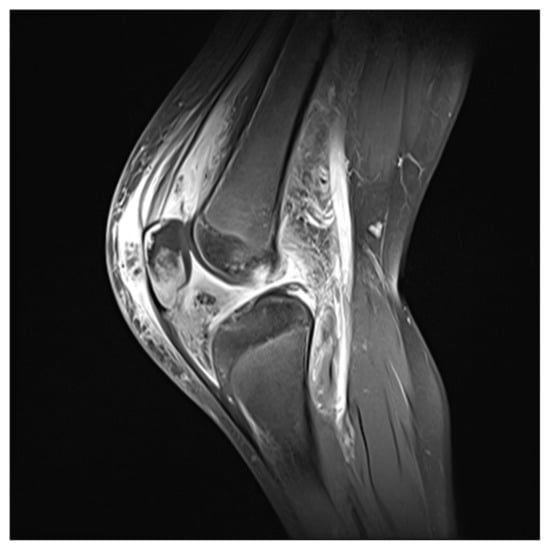

Patellar Osteomyelitis in a 9-Year-Old Patient with Chronic Granulomatous Disease: A Case Report

2. Case Report